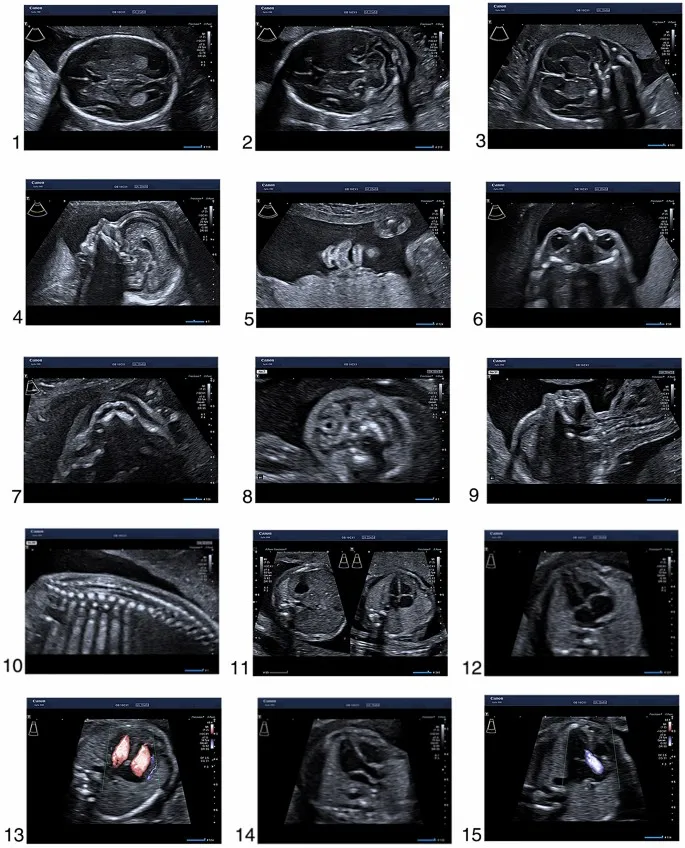

- Tests: Ultrasound (for anomalies) + Maternal serum screening.

- Sonographic Markers (NT Scan):

- ↑ Nuchal Translucency (NT)

- Absent/Hypoplastic Nasal Bone

- Nuchal Translucency (NT) is the most important first-trimester ultrasound marker for Down syndrome.